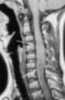

Bony spinal bar

A spinal cord injury (SCI) is damage to the spinal cord that causes temporary or permanent changes in its function. Symptoms may include loss of muscle function, sensation, or autonomic function in the parts of the body served by the spinal cord below the level of the injury. [Source: Wikipedia ]